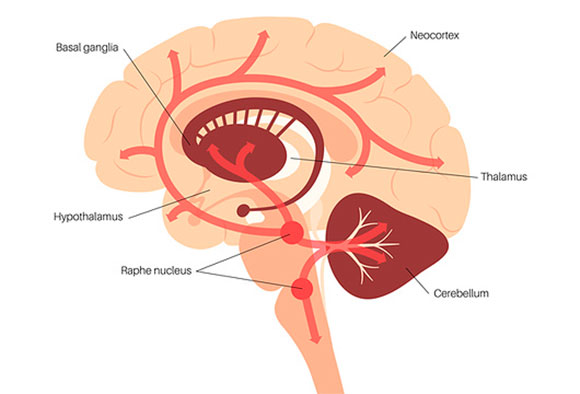

Serotonin is implicated in our state of mind, but it does not singularly dictate our feelings. Illustration of the brain areas where serotonin is active | PIKOVIT, Science Photo Library